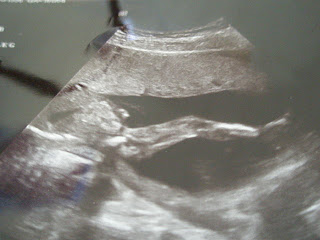

Here are the pictures of two little babies from the OBG visit.

I forgot which baby, but this is LEG! She is stretching it out! @16 weeks |